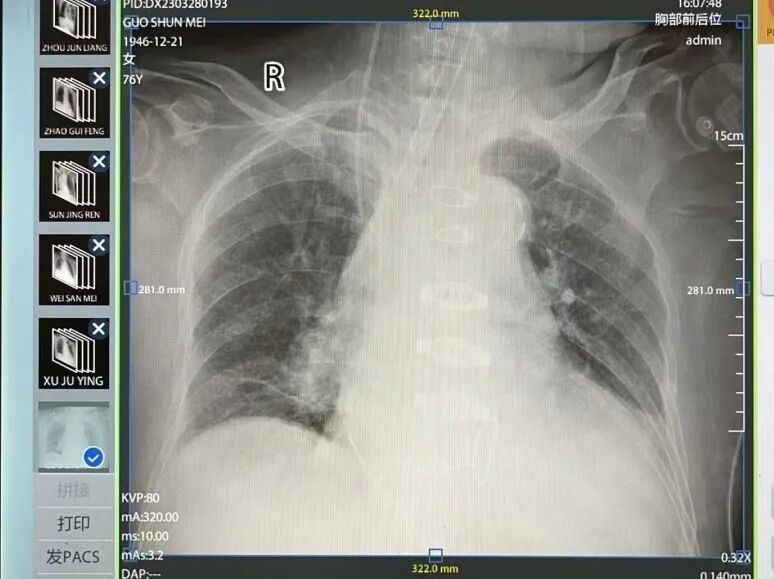

近日,罹患心脏病多年的76岁女性患者郭某顺利转出重症监护病房,开始接受术后康复治疗,标志着我院开展的首例人工心脏瓣膜置换手术取得成功。这也是溧水区首次开展此类高难度的心脏外科手术。 01 “心”病难医 据了解,患者郭某长期患有高血压病,8年前开始出现活动后胸闷不适,多次心内科住院治疗,诊断为“主动脉重度关闭不全、二尖瓣中度关闭不全、心功能III级”。反复保守治疗效果不佳,已经严重影响生活质量,甚至危及生命。我院胸外科会诊后建议患者选择外科手术治疗。 术前,我院胸外科、心内科、麻醉科、重症医学科以及东南大学附属中大医院的相关专家专门针对该患者病情和手术计划开展了多学科讨论,一致认为患者有瓣膜置换的手术指征,而我院已具备开展该手术的条件和专家团队,可以实施此类手术。 02 开启“心”项目 “我们从未开展过此类手术,这在全区来说也是首例,不过我们有信心把手术做好。”我院胸外科主任刘峰说。 刘峰的信心来自于东南大学附属中大医院专家的鼎力支持。我院自与中大医院深化合作以来,中大医院从医院管理、医疗、教学、科研等方方面面与我院深度融合发展,给予了多层次、多形式、多方位的倾力支持。多年的院府合作,医院的管理水平、服务能力、技术水平得到了显著提升,合作后带来的优质医疗资源下沉也让溧水百姓在“家门口”享受到了三甲医院的医疗服务。 03 突破“心”技术 3月27日,经院党委书记陈明、院长高增鑫和副院长吴剑平等院领导的协调,在东南大学附属中大医院多科室专家的全力配合下,由东南大学附属中大医院心胸外科刘志勇副院长、何伟主任医师和我院胸外科刘峰主任医师领衔的“中大-溧医”心胸外科手术团队成功为郭某开展了体外循环下主动脉瓣生物瓣置换术+二尖瓣成型术,手术仅用时约4小时。 术后,患者转入ICU,在东南大学附属中大医院专家、重症医学科刘松桥主任及多科专家严密的监护治疗下,患者心功能指标及生命体征逐步稳定,已符合转入普通病房的指征。 长期以来,心脏手术被视为外科领域“宝塔上的明珠”。由于其手术风险高、死亡率高,此类手术常常只能在省级以上大型医院开展。我院成功开展体外循环下人工心脏瓣膜置换手术,标志着医院在心胸外科领域迈入更高水平的行列。 未来,在东南大学附属中大医院的帮扶和支持下,我院将继续拓展医疗新技术和新项目,持续提升医院重症疑难杂症的诊疗水平,让群众就近享受到便捷优质的医疗服务。